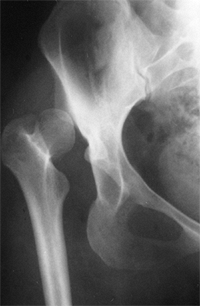

![]() |

Figure 24.6 Untreated dislocation of the hip. Note the lack of the concave shape and the shallowness of the acetabulum.